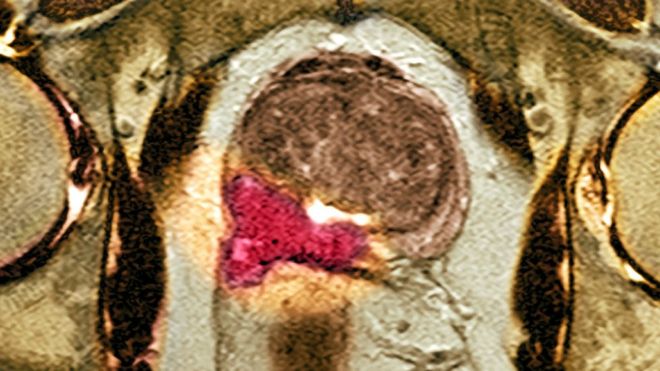

Мужчины и женщины могут сделать МРТ малого таза с контрастированием в клиниках СПб только по показаниям врача. Оно необходимо, чтобы обнаружить доброкачественные и злокачественные опухоли, различные инфекции. Контрастное вещество очень хорошо подсвечивает больные участки на снимках, за счет чего их легче распознать.

Необходимо знать, что даёт МРТ малого таза увидеть на снимках, чтобы быть полноценно осведомлённым о заболевании. Наличие злокачественной опухоли — неутешительный диагноз для пациента. Для полноценного излечения от недуга следует сделать качественное обследование. В настоящее время к сожалению процент возникновения раковых новообразований органов малого таза, у женской половины человечества стремительно растёт. Выявленная опухоль во многих случаях проявляет метастазы (вторичное проявление заболевания). Врачебная статистика показывает, что большинство опухолей метастизируют по каналам лимфооттока. Первичная зона поражения - региональные лимфоузлы, а далее — уже отдалённые.

Современные установки МРТ выявляют самые микроскопические метастазы в лимфоузлах. Вас мучает вопрос, что даёт МРТ малого таза, и в чем отличия от СКТ. Преимущество МРТ заключается в том, что можно с доскональной точностью определить стадию развития злокачественной опухоли. Необходимо ли МРТ лимфатических узлов малого таза или нет? Освещая этот вопрос следует отметить, что крайне важно выявить все очаги поражения недугом. Увеличение лимфоузлов, что выявляет МРТ малого таза, свидетельствует о наличии метастаз раковой опухоли. Детальная расшифровка позволяет врачам определиться, какое лечение назначить пациенту, и есть ли шанс использовать радикальное лечение (хирургическое вмешательство).

Следует отметить, что МРТ мужского таза может проводится двумя основными методами: с дополнительным введением нетоксичного контрастного вещества и без него. МРТ малого таза у мужчин с контрастом позволяет определить четкие границы и края имеющейся опухоли или мельчайшие метастазы и изменения в тканях. Контраст вводится внутривенно.